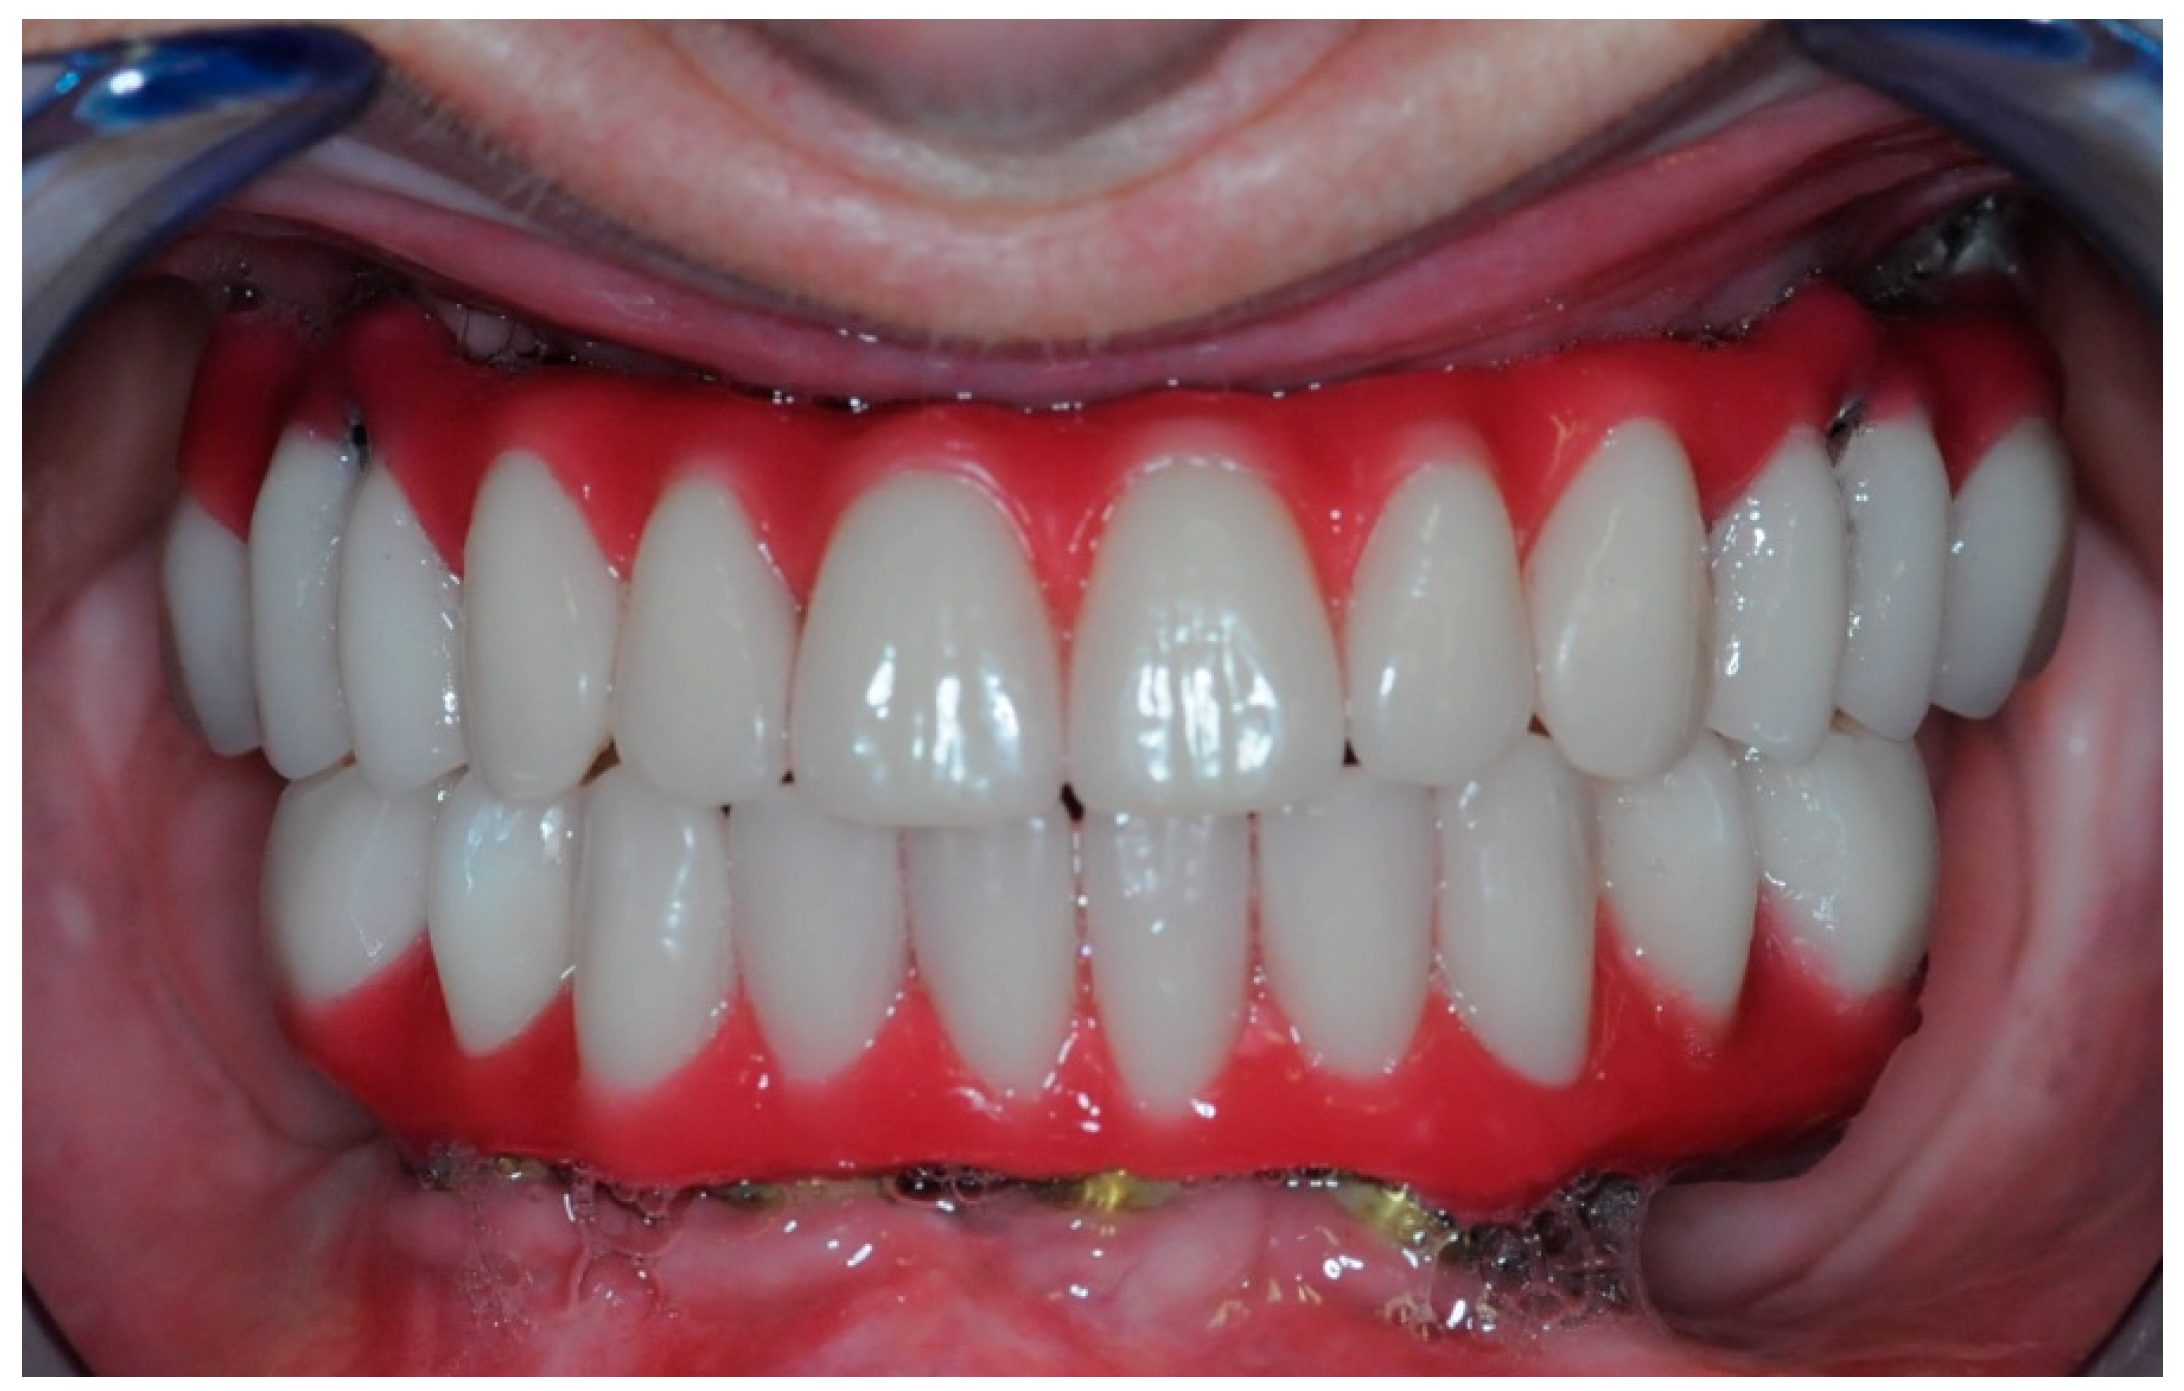

2.5. Final Prosthesis

3. Results

3.5. Function and Aesthetics